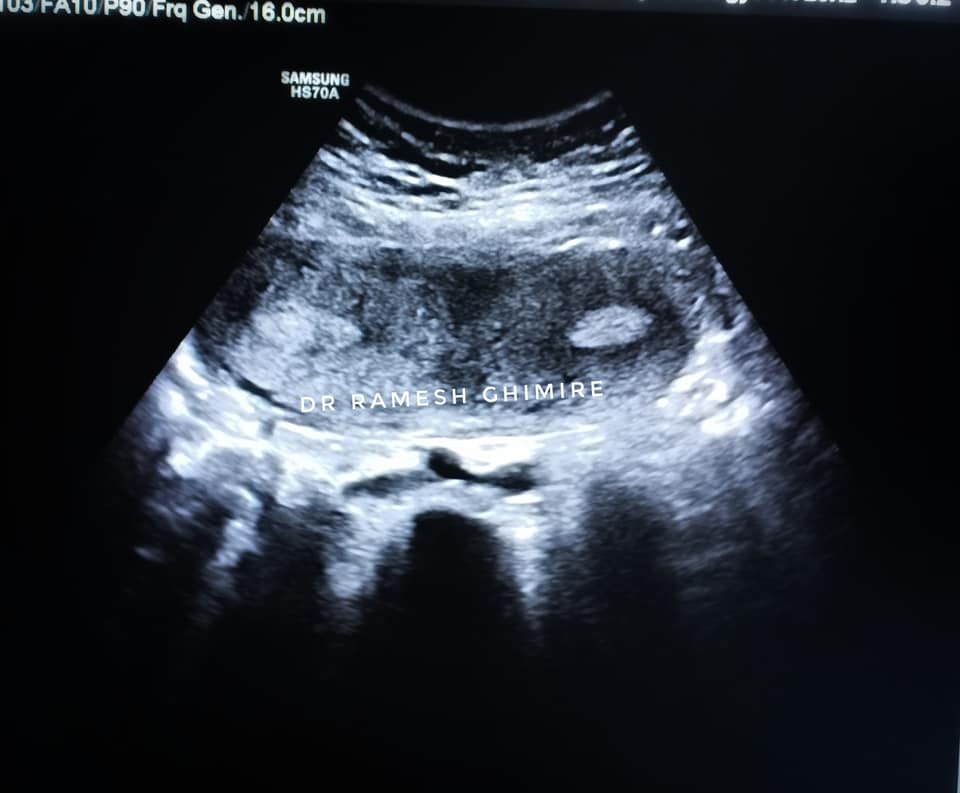

तस्वीर : मौलाकालिका अस्पतालको फेसबुक पेजबाट

काठमाडौं । एक महिलाको शरिरमा दुईवटा पाठेघर भएको पाइएको छ । चितवनको मौलाकालिका अस्पतालमा त्यस्तो केस भेटिएको हो ।

गर्भमा बच्चा नबसेको भन्दै आएकी एक महिलाको शरिरमा दुईवटा पाठेघर भेटिएको डा रमेश घिमिरेले लोकपथलाई जानकारी दिए । ती महिलाको शरिरमा भएको दुई वटा पाठेघर ‘४डी’ टेक्नोलोजीमार्फत पत्ता लागेको उनले बताए । त्यस्ता केसहरु आइरहने पनि उनले बताएका छन् । “प्राय यस्ता केसहरु आइरहेका हुन्छन् । तर त्यसको पहिचान ४डी प्रविधिबाट मात्रै पहिचान गर्न सकिन्छ ।” उनले भने ।